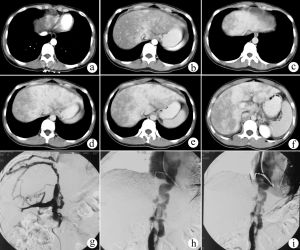

布-加氏綜合徵的影像學診斷是最重要的診斷方法。非創傷的檢查方法主要為超聲,CT和MRA。其中超聲,特別是都卜勒超聲是經濟而有效的診斷方法,主要顯示肝,脾腫大,肝靜脈和下腔靜脈的阻塞的程度、範圍和血流方向等。CT平掃時可顯示肝脾腫大等。值得注意的是淤血肝臟的密度不均勻,出現不規則低密度灶,有時可誤診為肝癌,肝脂肪變等。肝尾狀葉肥大對本症有提示作用。良好的增強掃描和血管重建可較清楚顯示肝靜脈和下腔靜脈狹窄和閉塞的情況。下腔靜脈和(或)肝靜脈造影為本病診斷的金標準。

4、CT掃描在BuddChiari綜合徵急性期,CT平掃可見肝臟呈瀰漫性低密度腫大且伴有大量腹水。CT掃描的特異性表現是下腔靜脈肝後段及主肝靜脈內出現高度衰退的充盈缺損(60~70Hu)。增強掃描對BuddChiari綜合徵的診斷具有重要意義。注射造影劑後30s,可見肝門附近出現斑點狀增強(中心性斑點區),肝臟周圍區域增強不明顯,並且出現門靜脈廣泛顯影,提示門靜脈血液離肝而去。注射造影劑後60s,肝內出現低密度帶狀影繞以邊緣增強,或稱之為肝靜脈和下腔靜脈充盈缺損,此種徵象高度提示管腔內血栓形成,邊緣增強是由於血管壁滋養血管顯影所致。

1、布-加氏綜合徵的超聲特點從本組資料觀察布-加氏綜合徵有以下特點:肝靜脈近段狹窄或閉塞,內有膜性或實質性阻塞物,狹窄處血流變細,閉塞時血流消失,遠段血流淤滯擴張,擴張的肝靜脈血流方向異常或速度減慢。肝靜脈間交通支形成、擴張,副肝靜脈開放擴張。都卜勒可見肝靜脈狹窄處呈花彩血流,流速增加,頻譜異常,三相波消失呈平直形。下腔靜脈近心段狹窄或閉塞。表現局部管腔變細、消失,管腔內有膜性、實質性梗阻物或腔外有腫瘤壓迫。下腔靜脈狹窄處近側呈花彩血流,速度增快,本組最高流速達260cm/s,或管腔內無血流信號。狹窄遠側管腔擴張,周圍側支循環豐富,血流方向異常流入側支。下腔靜脈波動消失,頻譜平直。